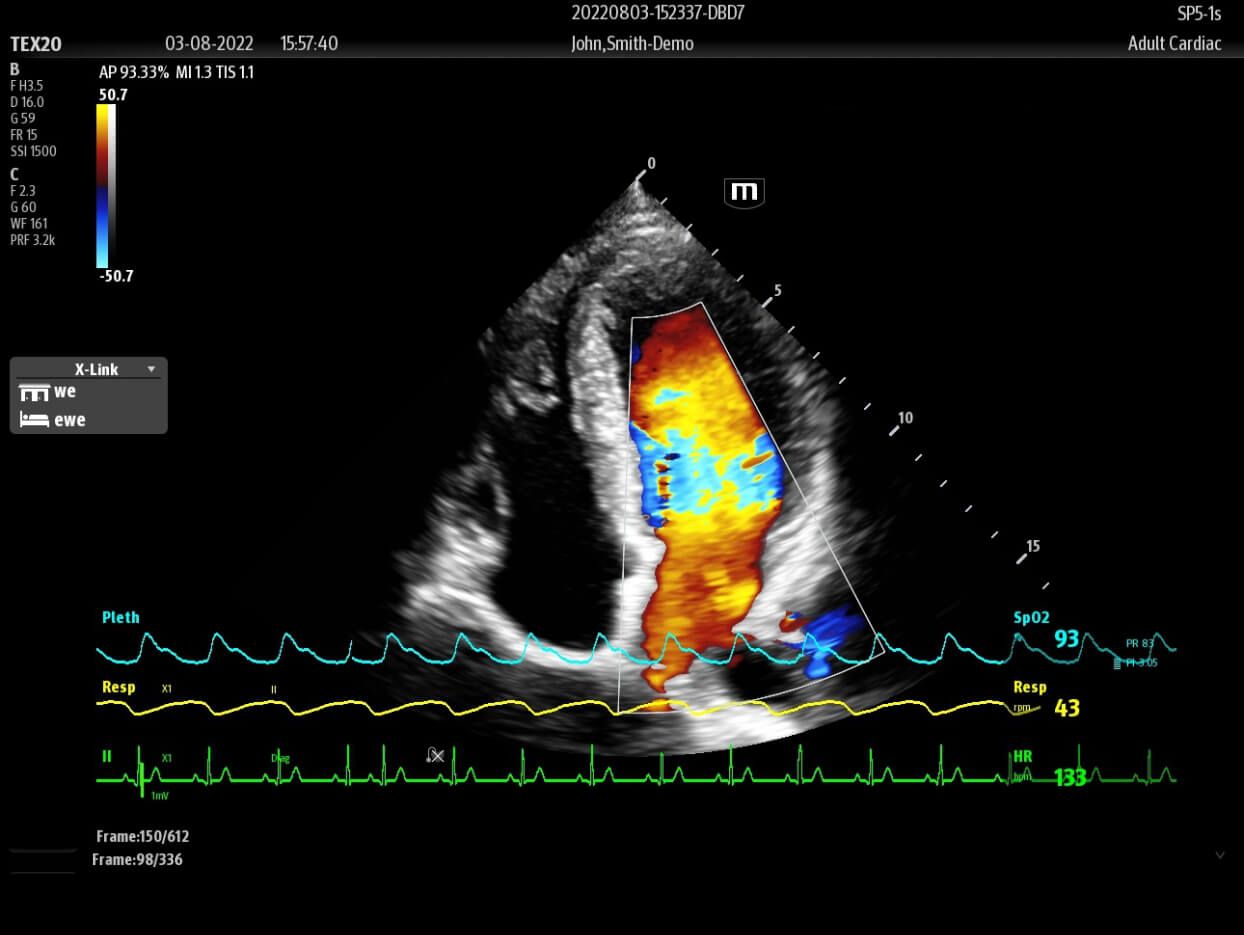

The TEX20 Series ultrasound system helps clinicians reimagine their clinical practice in demanding point-of-care environments like critical care, emergency medicine, and anaesthesia.

Based on the professional society guidelines for point of care ultrasound, the X-Pilot suite integrates historical diagnostic images and multi-organ data into a concise and precise view of the patient status to support rapid clinical decisions at the bedside.